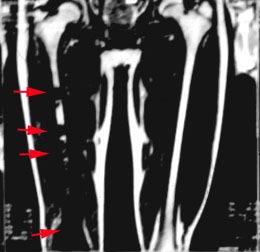

6 核磁共振(MRI)檢查。

6 X線攝片:基本表現為新生骨形成和溶骨性破壞相結合。在長管骨幹腄端偏心性骨質疏鬆,繼之溶骨性破壞和骨質硬化,邊緣模糊。當骨皮質破壞,可見軟組織陰影和不規則的骨膜反應,呈codman氏三角或日光放射狀陰影。